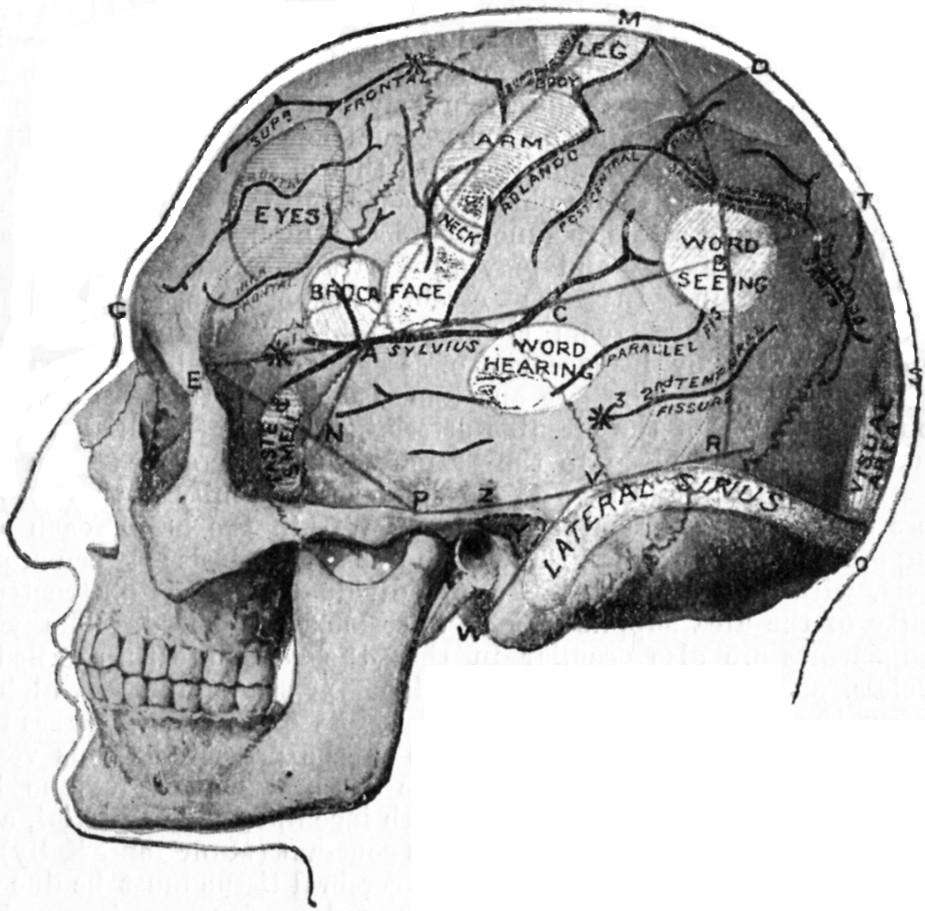

| 179. | Relations of the Motor and Sensory Areas to the Convolutions and to Chiene's Lines | 330 |

| 181. | Chiene's Method of Cerebral Localisation | 336 |